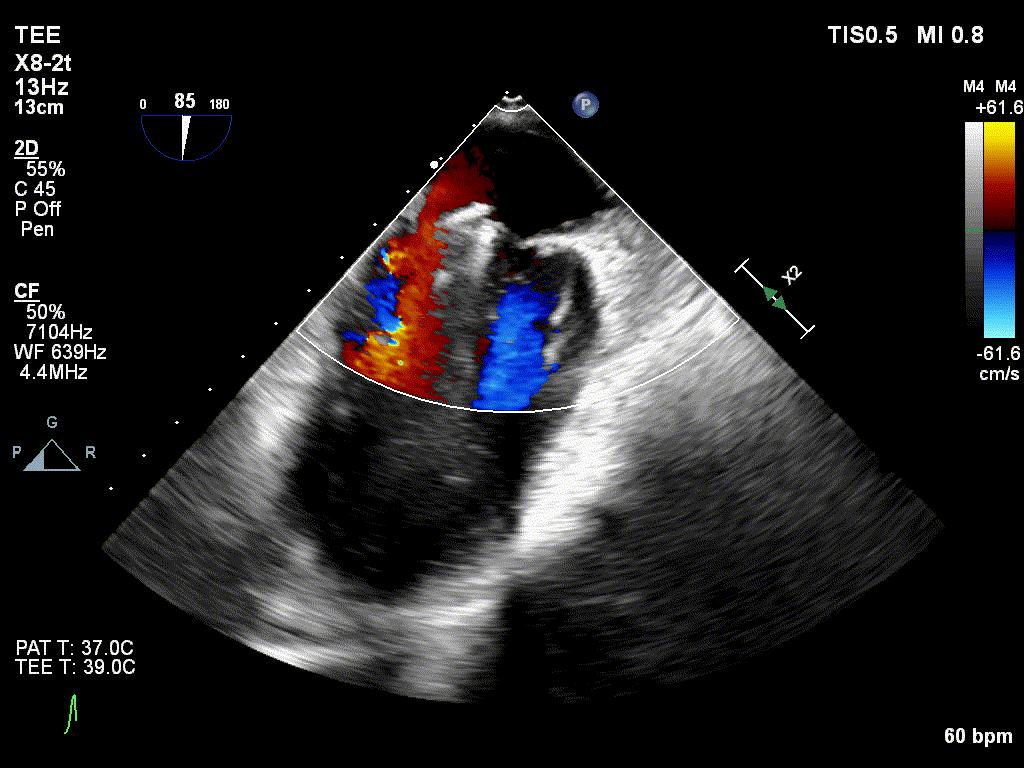

X-plane视图下对准反流束中心进入左室

穿刺右侧股静脉,预埋血管缝合器,食道超声指导下房间隔穿刺成功,将导丝送至左房建立轨道,沿导丝将导引导管送入左房,经输送系统将Mitraclip瓣膜夹顺利到达二尖瓣目标位置,在食道超声辅助下,精确定位后,使用1个clip成功夹合二尖瓣A2-P2区,彩色多普勒超声显示少量残余分流,整体反流量改善2级以上,手术圆满完成!